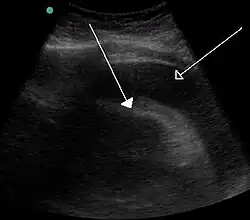

Bladder tamponade is obstruction of the urinary bladder outlet due to heavy blood clot formation within it.[3] It generally requires surgery.[3] Such heavy bleeding is usually due to bladder cancer.[4]